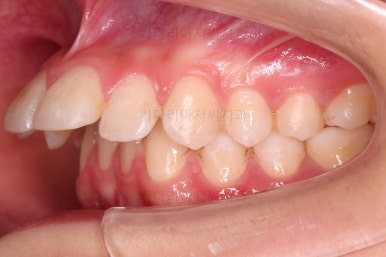

초진 시 입안의 모습입니다.

위아랫니가 많이 삐뚤진 않는데 뭔가 이상하죠?

어금니 맞물림은 지그재그로 잘 맞물려 있는데 위아래 앞니는 서로 앞뒤로 매우 멀죠.

비밀은 매우 자연스러워 보이지만 아래 앞니 2개가 선천 결손인 상태였습니다.

앞니가 매우 튀어나와 보이고요.

앞니끼리 맞물리지 않다보니 아래 앞니는 점점 솟구쳐 과개교합(깊게 맞물려 아래 앞니가 거의 보이지 않는 현상)이 되게 됩니다.